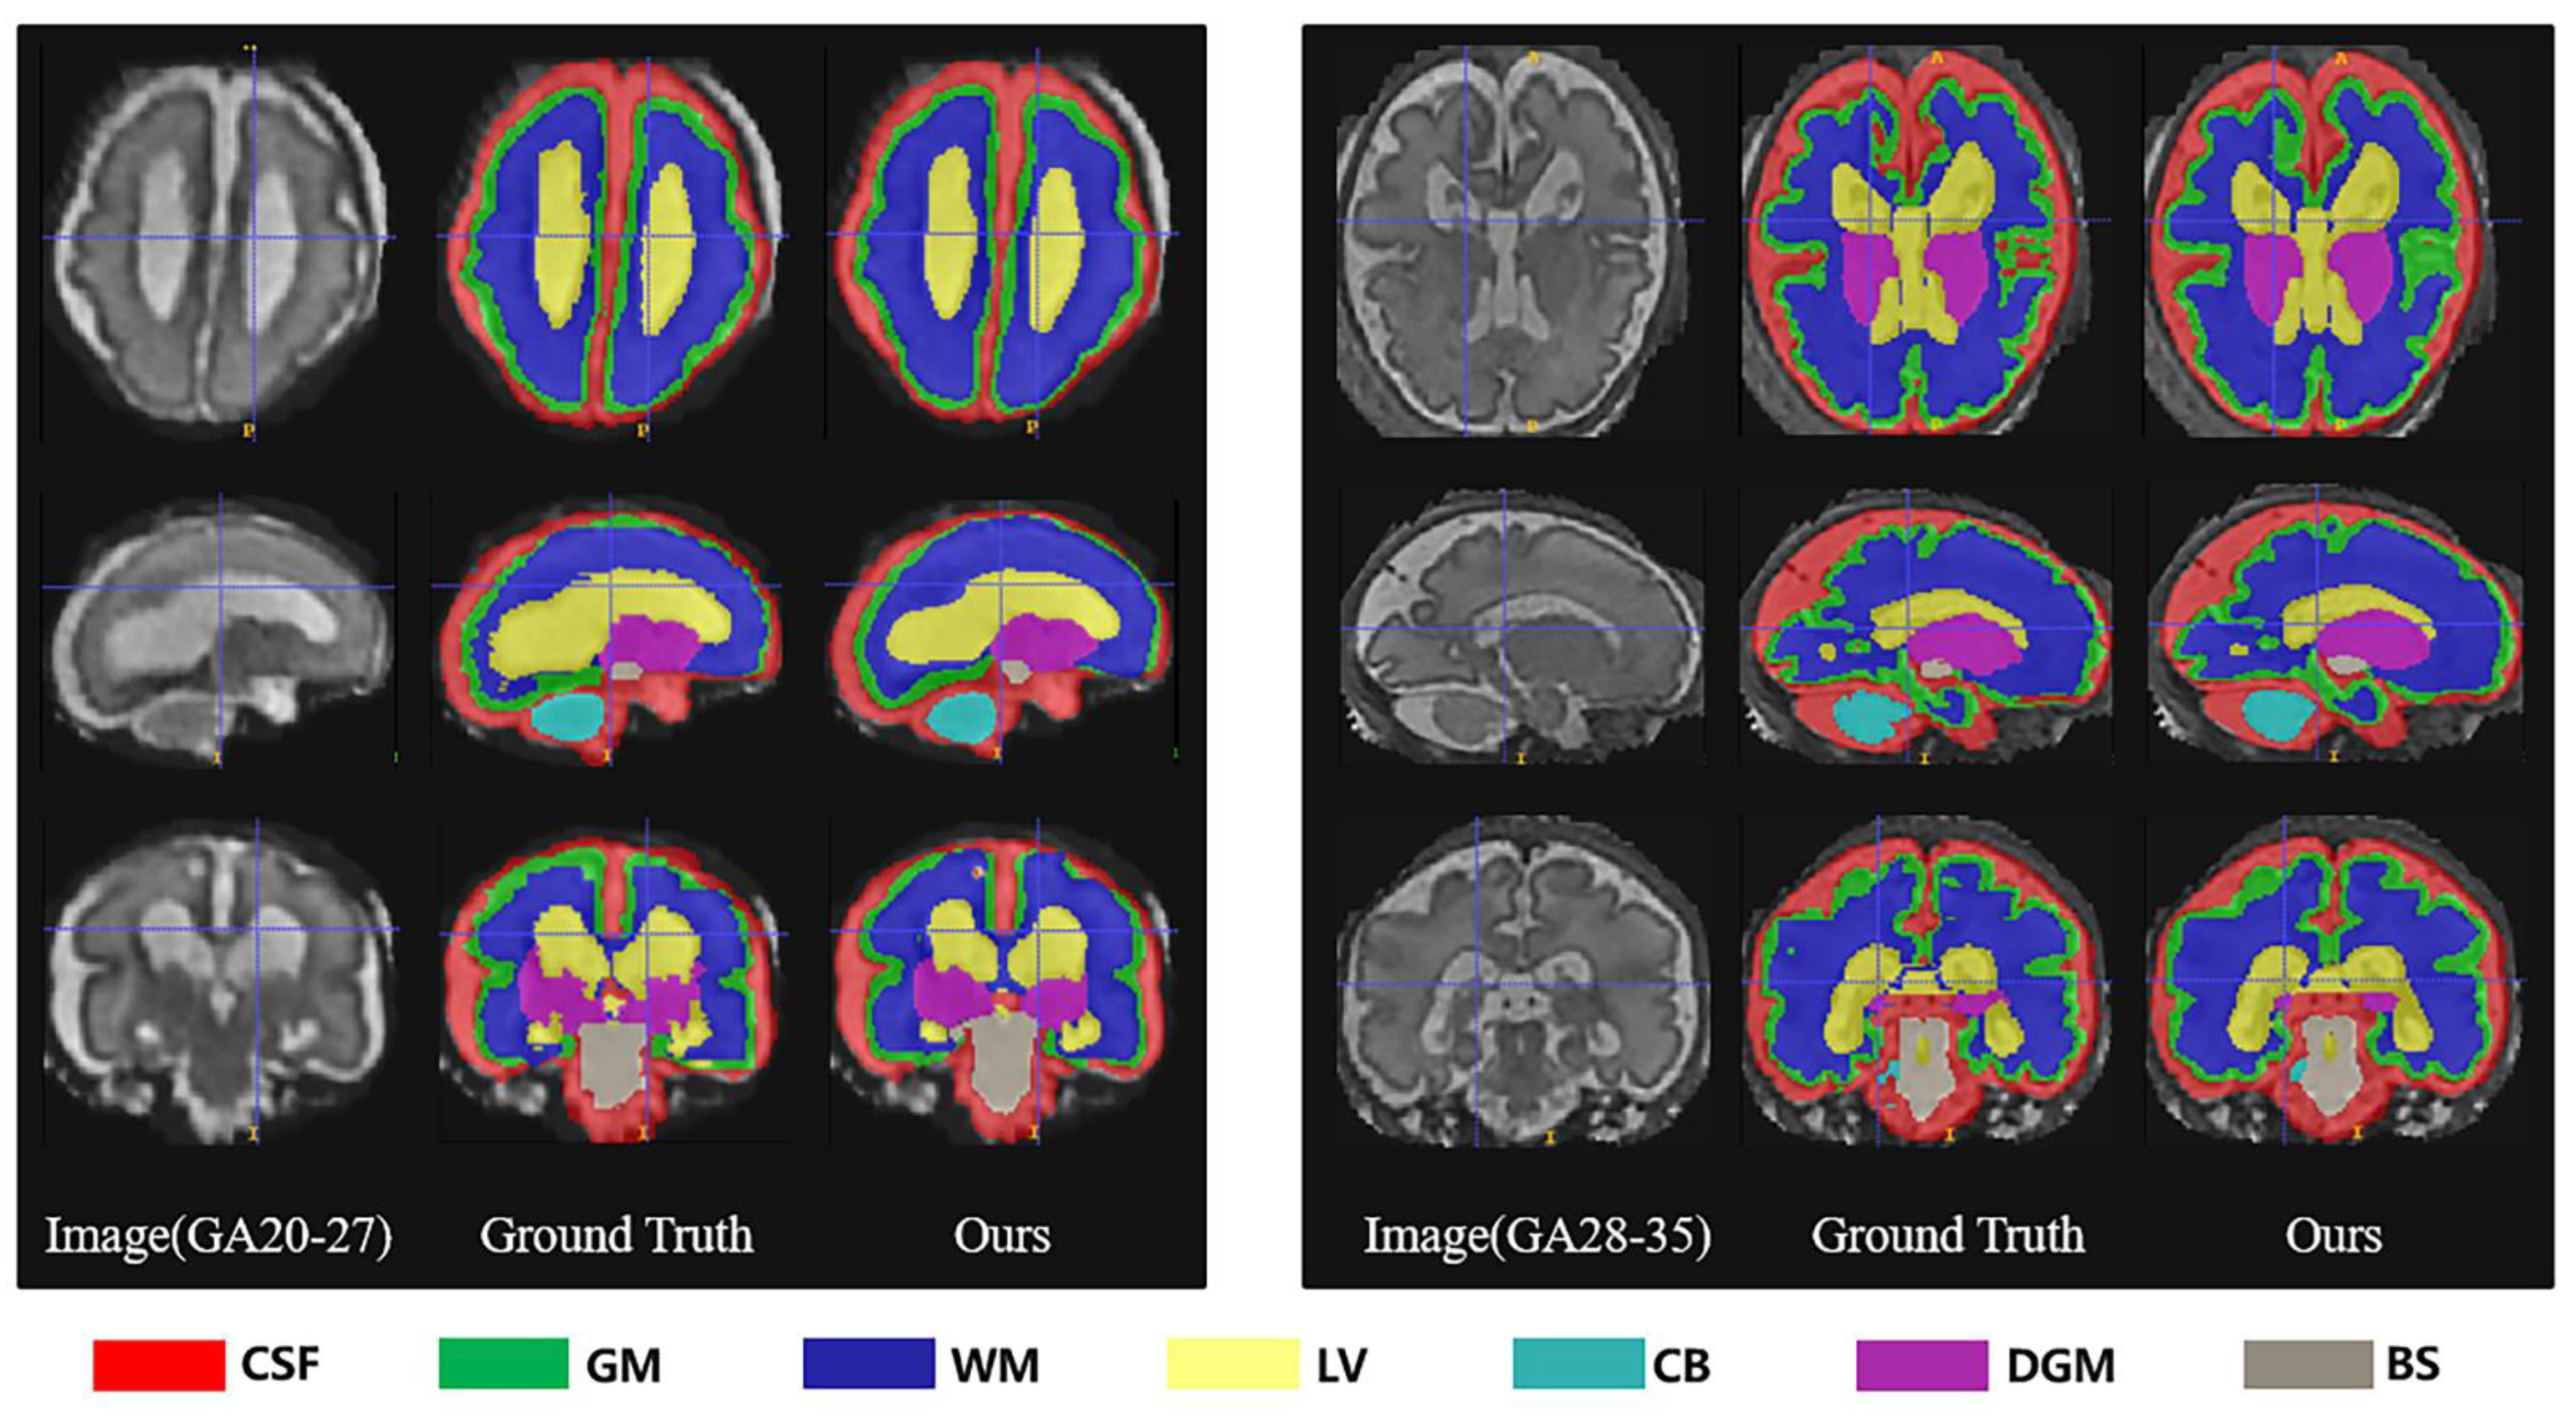

3.2. Gestational Age Analysis

| GA | Metrics | eCSF | GM | WM | LV | CB | dGM | BS | |

|---|---|---|---|---|---|---|---|---|---|

| 20–27 | DSC (%) | 87.49 8.31 | 83.61 1.29 | 95.66 0.43 | 90.59 3.29 | 92.13 0.29 | 94.37 0.50 | 85.30 2.79 | 89.88 2.41 |

| VS (%) | 89.05 6.94 | 85.46 1.24 | 96.18 0.40 | 91.82 2.72 | 94.08 0.31 | 95.44 0.49 | 89.00 1.78 | 91.58 1.98 | |

| HD95 (mm) | 22.64 3.08 | 22.91 1.38 | 24.39 1.52 | 33.52 2.03 | 55.97 2.55 | 40.82 1.58 | 52.54 3.18 | 36.11 2.19 | |

| PRE (%) | 91.48 3.32 | 85.78 0.81 | 96.26 0.30 | 90.72 2.62 | 94.58 0.71 | 96.23 0.92 | 89.36 0.74 | 92.06 1.35 | |

| SEN (%) | 87.01 0.10 | 85.14 1.82 | 96.11 0.51 | 92.94 2.88 | 93.59 0.84 | 94.68 0.27 | 88.67 2.79 | 91.16 1.32 | |

| SPC (%) | 99.44 0.35 | 99.43 0.05 | 99.45 0.19 | 99.77 0.14 | 99.96 0.01 | 99.94 0.01 | 99.96 0.01 | 99.71 0.11 | |

| 28–35 | DSC (%) | 92.04 0.88 | 76.41 3.86 | 94.68 0.70 | 77.98 3.93 | 93.09 0.68 | 94.27 0.61 | 87.17 1.68 | 87.95 1.76 |

| VS (%) | 92.78 0.87 | 78.38 3.56 | 95.23 0.65 | 81.35 3.55 | 94.70 0.70 | 95.38 0.59 | 90.59 1.56 | 89.77 1.64 | |

| HD95 (mm) | 20.50 1.83 | 23.47 1.36 | 24.69 1.35 | 37.26 2.43 | 53.71 1.96 | 39.77 1.65 | 50.94 2.82 | 35.76 1.91 | |

| PRE (%) | 92.73 0.01 | 79.43 3.15 | 95.00 0.84 | 80.97 5.37 | 95.14 0.53 | 95.64 0.39 | 90.51 1.77 | 89.92 1.72 | |

| SEN (%) | 92.83 0.76 | 77.37 3.99 | 95.45 0.52 | 81.85 1.79 | 94.27 1.30 | 95.14 1.31 | 90.68 1.87 | 89.66 1.65 | |

| SPC (%) | 99.05 0.08 | 99.12 0.16 | 99.30 0.11 | 99.91 0.02 | 99.95 0.01 | 99.92 0.01 | 99.96 0.01 | 99.60 0.06 |